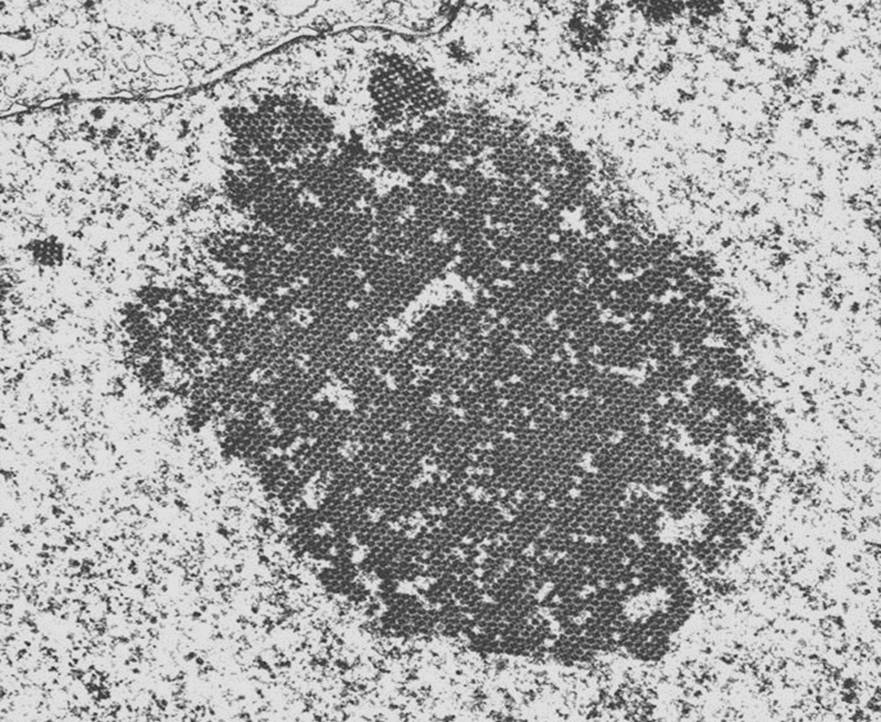

The final image is a EM image of an infected cell. Because BK-viral infection tends to be focal, it is unusual to actually see this appearance on EM. There is the appearance of a crystalline array of viral inclusions and in BK-virus, these tend to the in the range of 40-50 nm in size. In contrast, the inclusions in patients with adenovirus tend to be larger.